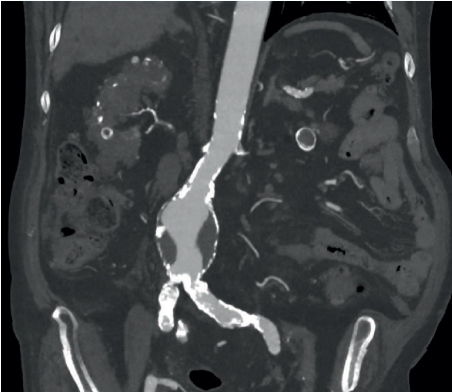

What is shown in the image below?

A

Saccular AAA